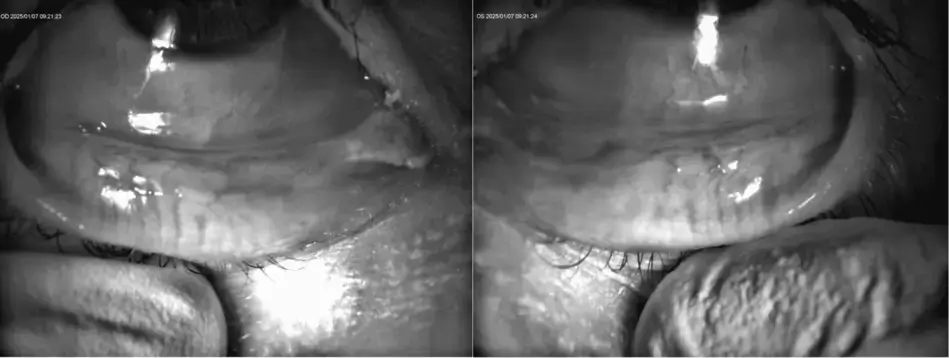

- Diagnostic principal : Chalazion Œil Gauche (OS)

- Autres observations bilatérales (OU) :- Blépharite à démodex grade 3+

- Dystrophie des glandes de Meibomius grade 2